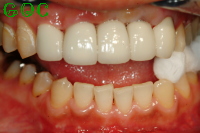

▼インプラント後![]() |

インプラントにしてたいへん満足しています。

噛んだ感触も自分の歯と変わらないほどです。

外観についてもこれ以上望めないほど、修復されたと思います。

家族や友人からは"天然の歯とまったく区別がつかない"と言われます。

審美的にも、入れ歯やブリッジと比較して一本一本が独立しているのでより自然に見えます。